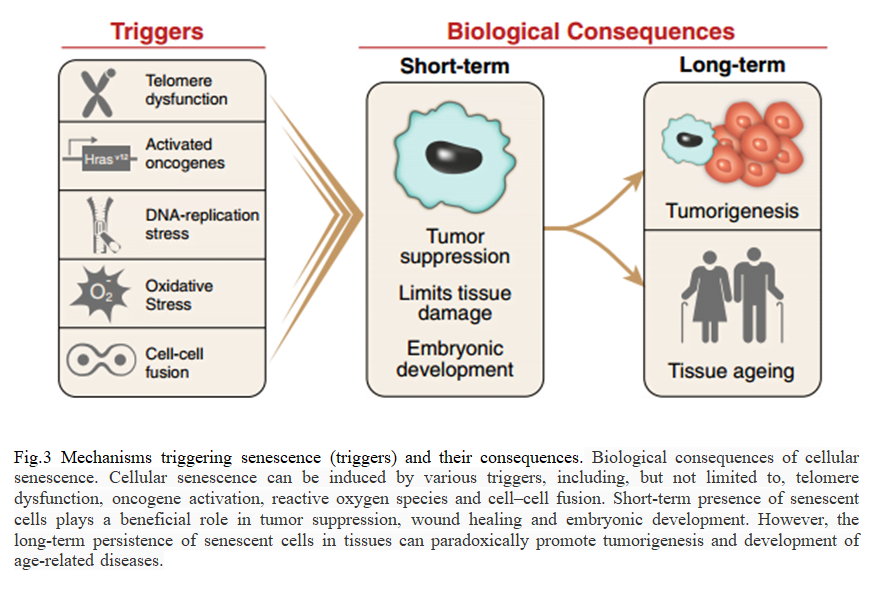

Cellular ageing is generally referred to as replicative senescence, a condition strictly linked to telomerase and telomere biology. Indeed, telomere shortening limited the replicative capacity of cells and the number of cells participating in tissue regeneration. Thus, the regenerative potential of an organ depends on the size of the population of cells with sufficient telomere reserves required for cell proliferation. Consistently, in chronic disease associated with tissue regeneration, such as cirrhosis, an elevated regenerative pressure is generated on the proliferating subpopulation of cells, which undergoes several rounds of cell division that, in turn, accelerate the rate of telomere shortening [17]. When telomeres become critically short, a DNA damage program is activated, leading to cell senescence or apoptosis (due to the Hayflick limit), further reducing the number of cell with regenerative capacity. In response to cellular stress, often resulting in DNA damage, proliferating cells can initiate a program that leads to a permanent cell cycle arrest termed cellular senescence. The short-term induction of cell senescence has beneficial roles in tumor suppression, wound healing and possibly embryonic development (Fig. 3). However, the long-term presence of senescent cells in tissues has the potential to promote age-related disease and cancer in a cell in non-autonomous manner[In response to cellular stress, often resulting in DNA damage, proliferating cells can initiate a program that leads to a permanent cell cycle arrest termed cellular senescence. The short-term induction of cell senescence has beneficial roles in tumor suppression, wound healing and possibly embryonic development (Fig. 3) [25]. However, the long-term presence of senescent cells in tissues has the potential to promote age-related disease and cancer in a cell in non-autonomous manner. In this review, we discuss the various triggers and mechanisms of cell senescence, the physiological and pathological consequences of the senescence program, the ability of senescent cells to interact with immune cells and provide possible explanations for why senescent cells may persist in tissues [25].